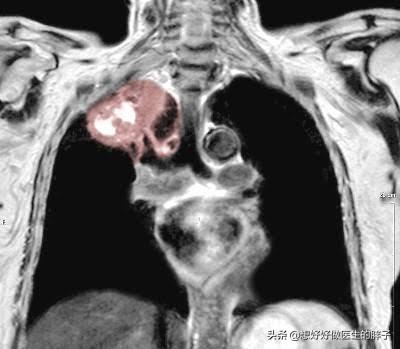

以上这些是排除掉心肌梗死或者心绞痛诱发的左肩疼痛的疾病诊断治疗的简单介绍。如果大家还有其他的疑惑,可以在下方留言,大家共同探讨,但是我们也要考虑到一些不常见的情况,比如导致左侧肩膀疼痛的原因,有可能是左侧的肺癌,这种情况多见于一种比较少见的癌症,我们称之为肺上沟癌(占肺癌的5%),当癌症默默生长的时候,并不会诱发特殊的症状,也不会导致患者出现咳嗽咳痰等情况,当肿瘤突破肺脏表面刺激到胸壁以后,会导致患者出现肩痛以及背痛,有数据显示有近16%的肺上沟癌癌症的患者首发症状是肩痛。